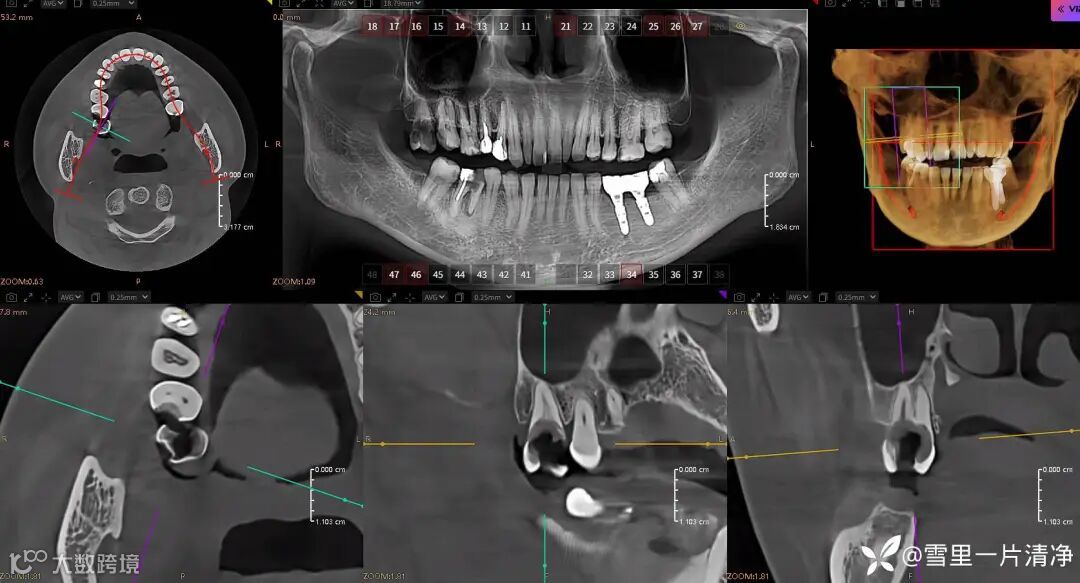

短短两年见到了他们迭代的速度非常的快,从2d的平面阅全景片,到3d的cbct阅片,到现在牙周阅片,我不得不感慨迭代速度更新频率比我现在玩的游戏还快。

针对全口的患者ai阅片,问题牙直接给你标红。

讲到到这里,ai给我带来的是全口牙病检查的便捷,咨询师利器